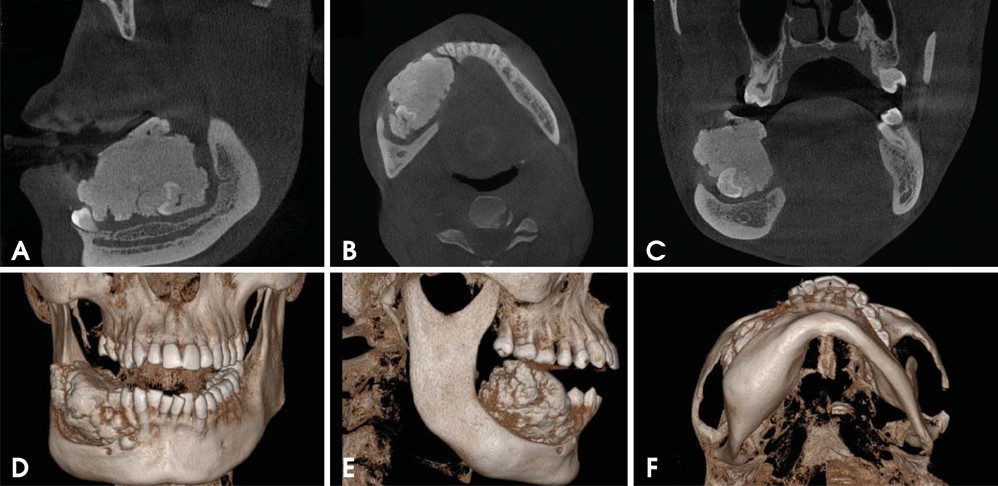

7. Phát hiện bệnh lý xương hàm:

CBCT giúp các bác sĩ phẫu thuật hàm mặt phát hiện, chẩn đoán, đánh giá độ lan rộng của các bệnh lý xương hàm xâm lấn như u nguyên bào men, nang sừng do răng, ung thư xương hàm, ….. từ đó lên kế hoạch điều trị cũng như vị trí mổ phù hợp.

U nguyên bào men được phát hiện trên phim CBCT